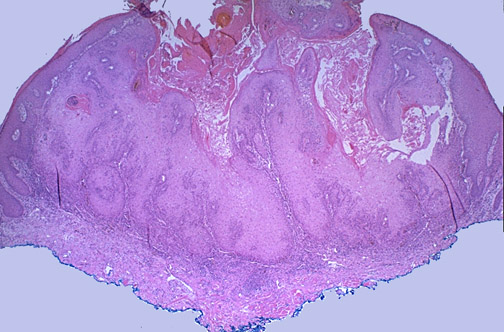

The low power view of an excised keratoacanthoma seen here shows the cup shaped pattern of growth, with a central area with keratin debris surrounded by proliferating squamous epithelium (the blue ink is used to mark the margins of the excision).